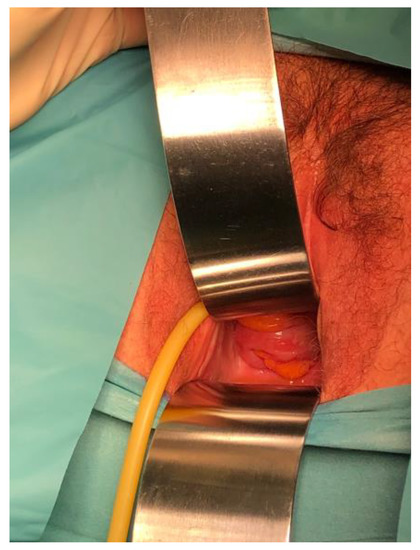

2.1. Case 1

2.2. Case 2